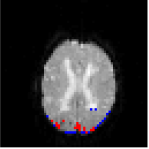

We apply our method to an event-related dataset. Buckner et al. (2000) used fMRI to study age-related changes in functional anatomy. The subjects were instructed to press a key with their right index finger upon the visual stimulus onset. The stimulus lasted for s. Functional images were collected using a Siemens -T Vision System with an asymmetric spin-echo sequence sensitive to BOLD contrast (volume TR = s, xy dimension: , voxel size: mm, 16 contiguous axial slices). Each run consists of TRs. For every images, the subjects were presented with one of the two conditions: (i) the one-trial condition where a single stimulus was presented to the subject, and (ii) the two-trial condition where two consecutive stimuli were presented. The inter-stimulus interval of was sufficiently large to guarantee that the overall response would be about twice as large as the response to the one-trial condition. We analyzed one run. After discarding the first and last four scans, the run included trials ( one-trial and two trial conditions) of temporal samples. Time series from the one-trial and two-trial conditions were averaged separately. Therefore, each voxel gave rise to two average time series of 8 samples. The linear trend was removed

from all average time series. The results published in (Buckner et al., 2000) show activation in the visual cortex, motor cortex, and cerebellum. We focus our analysis on four contiguous axial slices (7, 8, 9 and 10) that extend from the superior caudate nucleus to the midlevel diencephalon. We extract a region ( intracranial voxels) that extends from the occipital posterior horn of the lateral ventricles until the end of the occipital lobe. The total number of time series included in our analysis is : two time series (one-trial and two-trial conditions) of samples for each voxel.

have an abrupt dip at . The corresponding voxels are located

along the border of the brain (Fig. 17). The original

time series (before averaging) suffer from a sudden drop at time 95,

(Fig. 16-B and C), and the corresponding voxels

are located in the visual cortex (Fig. 17). Therefore,

of cluster II according to the strength of the activation: from two-trial condition (strong response) at the tip, to one-trial condition (weak response) at the stem (close to the background time series). This is a remarkable result since no information about the stimulus, or the type of trial was provided to the algorithm. Fig. 17 shows the location of the voxels corresponding to the time series of cluster I (blue) and II (red). For comparison purposes we computed the activation map obtained using the GLM. The averaged time series from the two-trial condition are used for the regression analysis. We use the hemodynamic response function defined by (Dale and Buckner, 1997), , where , . The regressor was given by , where is the stimulus time series. We thresholded the -value at , and the activation maps are shown in Fig.17. The activation maps constructed by our approach are consistent with the maps obtained with a GLM.